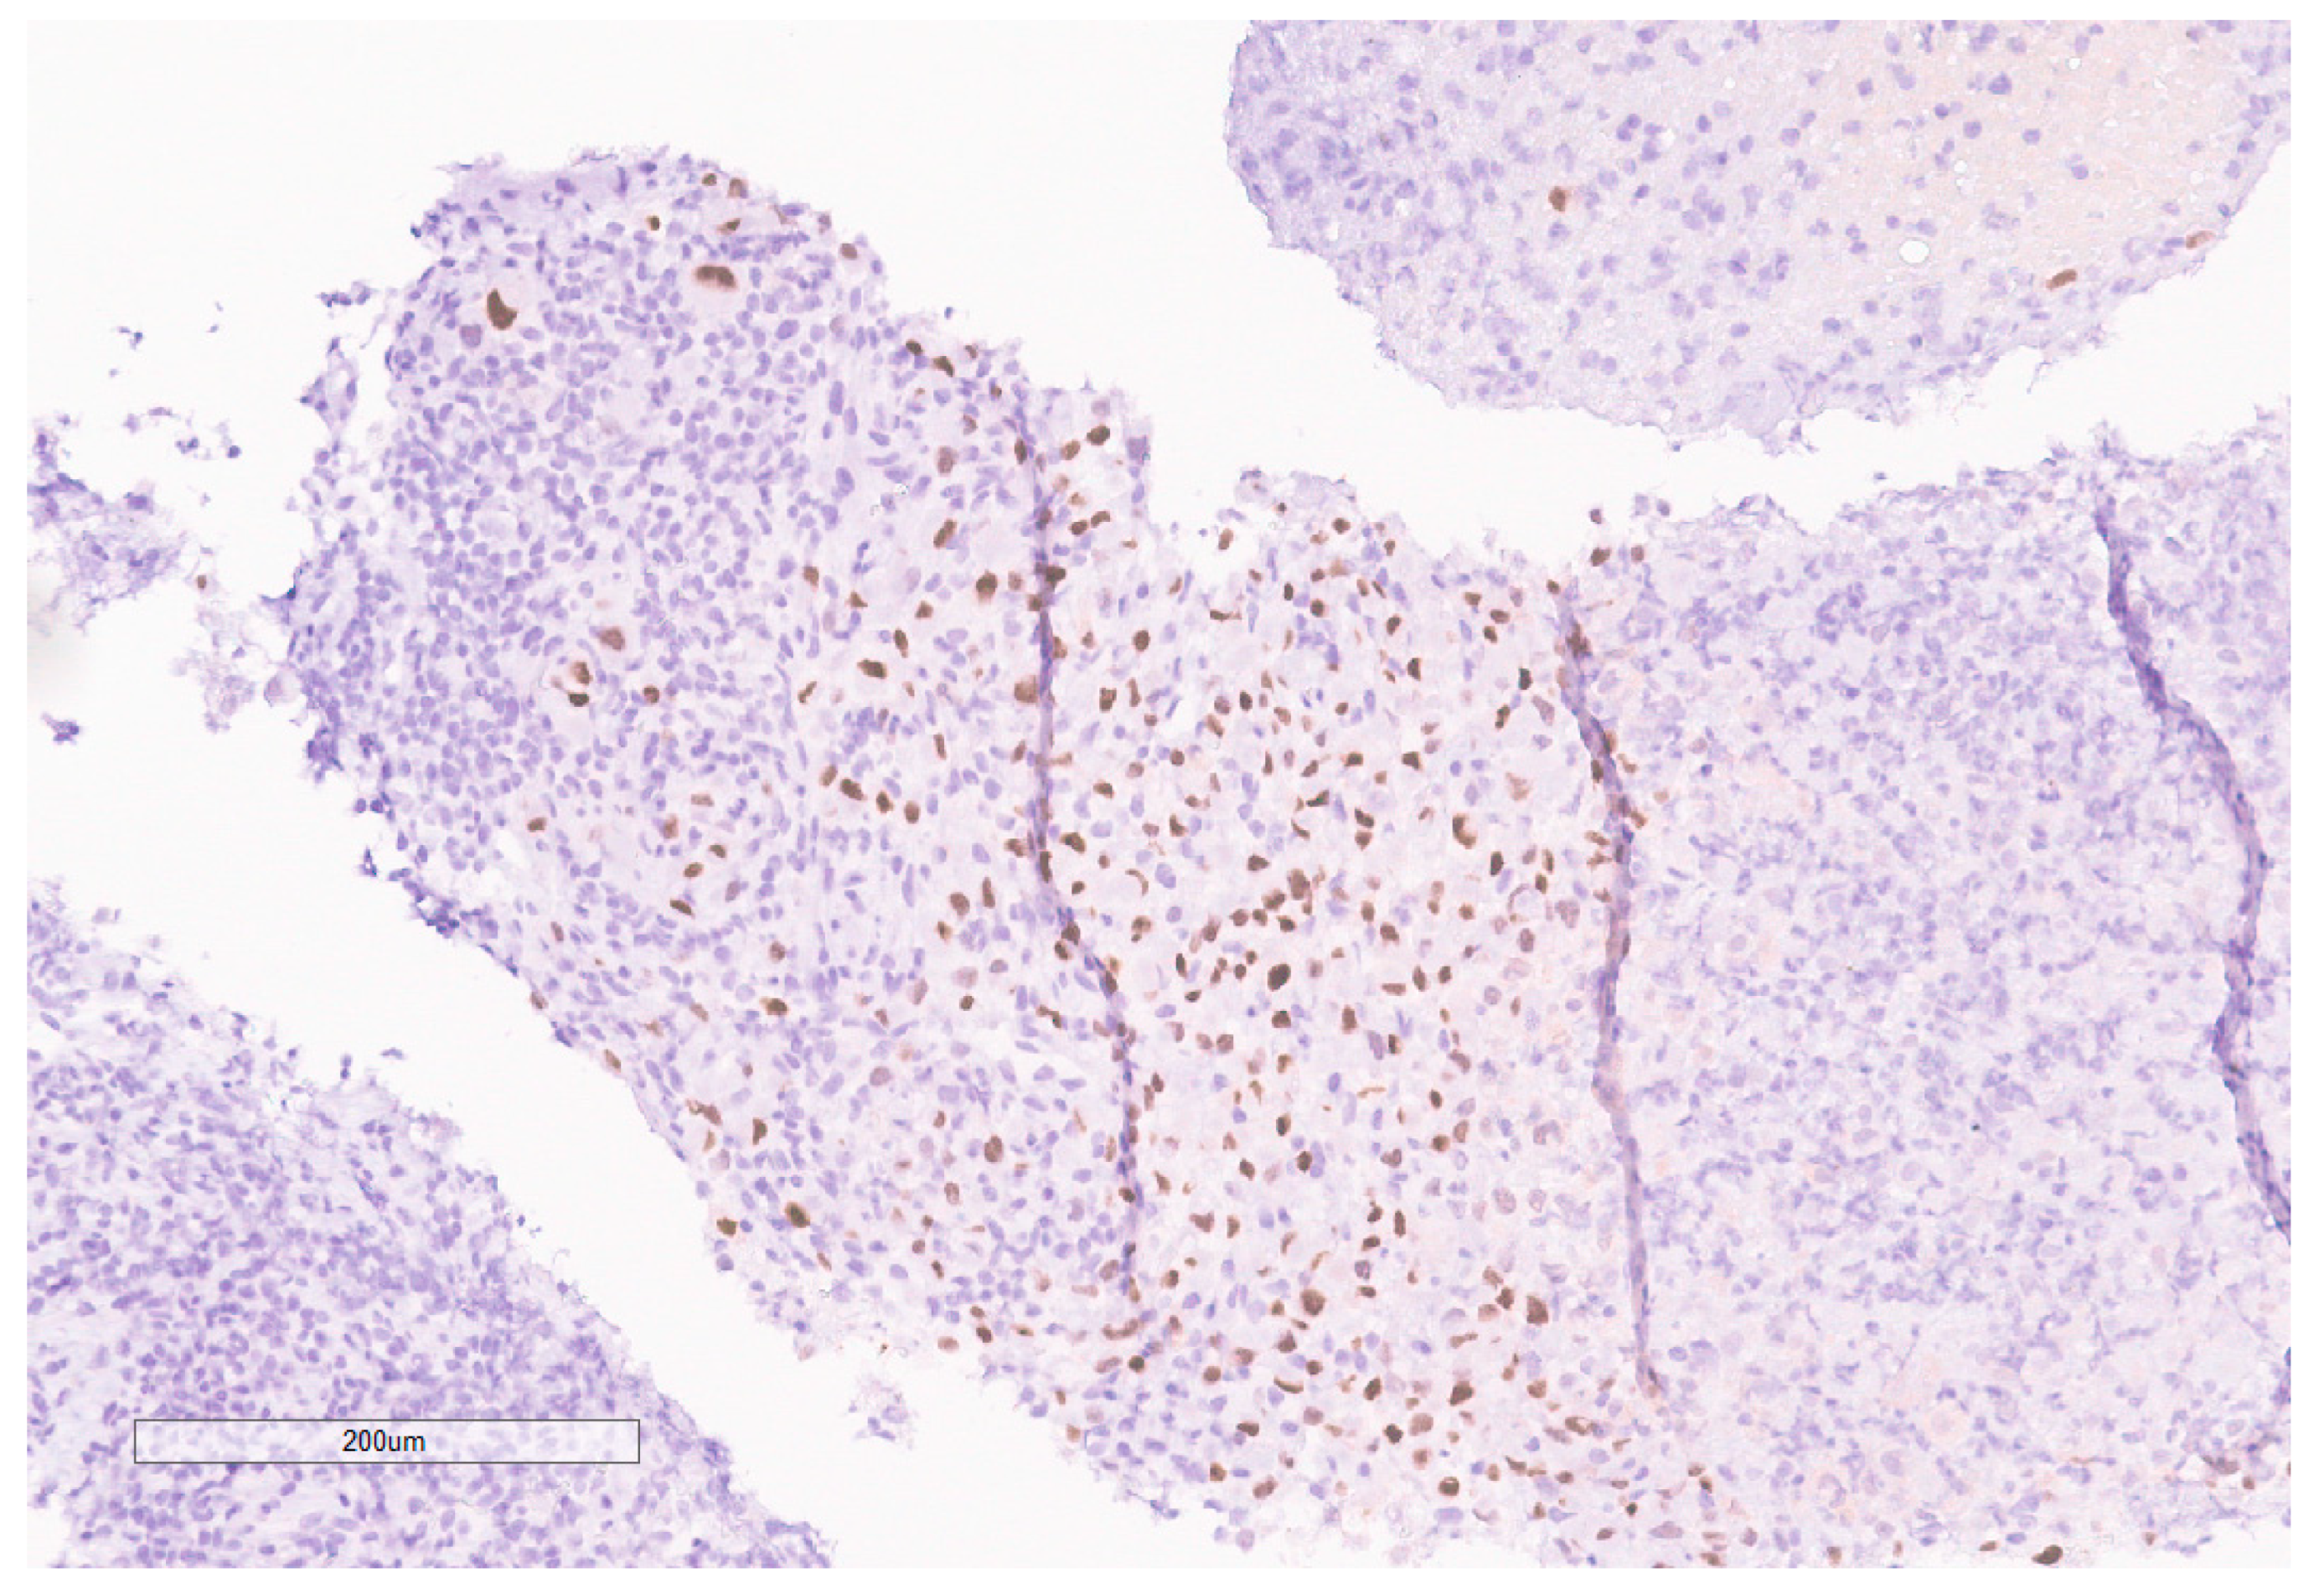

The biopsy of right kidney demonstrated mostly fibrinous material with small fragments of renal parenchyma with interstitial chronic inflammation and no definite tumor. The biopsy of a retroperitoneal lymph node showed high grade tumor composed of discohesive rhabdoid cells with highly atypical nuclei and eosinophilic cytoplasm involving lymphoid tissue with areas of necrosis and neutrophilic inflammation with necrosis and limited viable tumor cells (Figure 7). By immunohistochemistry, the cells were positive for pankeratin (Figure 8) and PAX8 (Figure 9) and negative for CK7, CK20, GATA3, CDX2, TTF1, CAIX, ERG, S100, CD34, CD30, SMA, desmin, OCT3/4 and CD163. The tumor cells showed diffuse loss of SMARCB1/INI-1 (Figure 10). The INI-1 was reviewed by several experienced pathologists that interpreted the stain as negative. While there is some background cytoplasmic and nuclear staining in the entire specimen, the norm is to compare staining with the adjacent internal positive control. Given that, in this case, the lymphocytes stained strongly positive for INI-1, it was appropriate to interpret this is as a negative stain in this context. As evidenced by the high-power image, the staining appears to be of a background variety and limited to the cytoplasm, in which the nuclei remain negative. Hence, this is interpreted as a negative stain.

Figure 9. PAX8 is positive in the tumor.

Figure 10. INI-1 (BAF47) is negative in the tumor. Lymphocytes serve as an internal positive control.

Given the expression of PAX8, and loss of SMARCB1 in the neoplastic cells, a diagnosis of RMC was favored. Malignant rhabdoid tumor (MRT) of the kidney was also considered due to the rhabdoid morphology in the setting of SMARCB1 loss. However, MRTs are typically negative for PAX8 and our specimen showed diffuse PAX8 staining. Furthermore, MRTs typically occur in children younger than 3 years old [11]. Hemoglobin electrophoresis was negative for sickle cell traits or other detectable hemoglobinopathies favoring the diagnosis of the RCCU-MP subtype of RMC. NGS of the tumor specimen did not identify copy number variants or somatic mutations. This NGS based its analysis for the detection of somatic mutations on the coding sequence of 134 genes and selected copy number variations or amplifications in 47 genes, for a total analysis of 146 genes with overlap. This was performed on DNA extracted from the sample in a clinical laboratory improvement amendment (CLIA) certified molecular diagnostic laboratory. This genetic analysis included analysis of NF2.